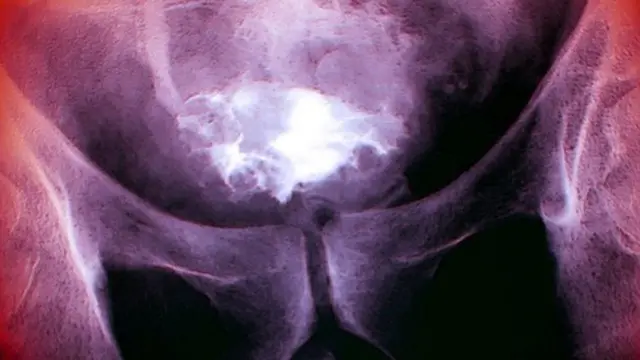

Crédit photo, Science Photo Library